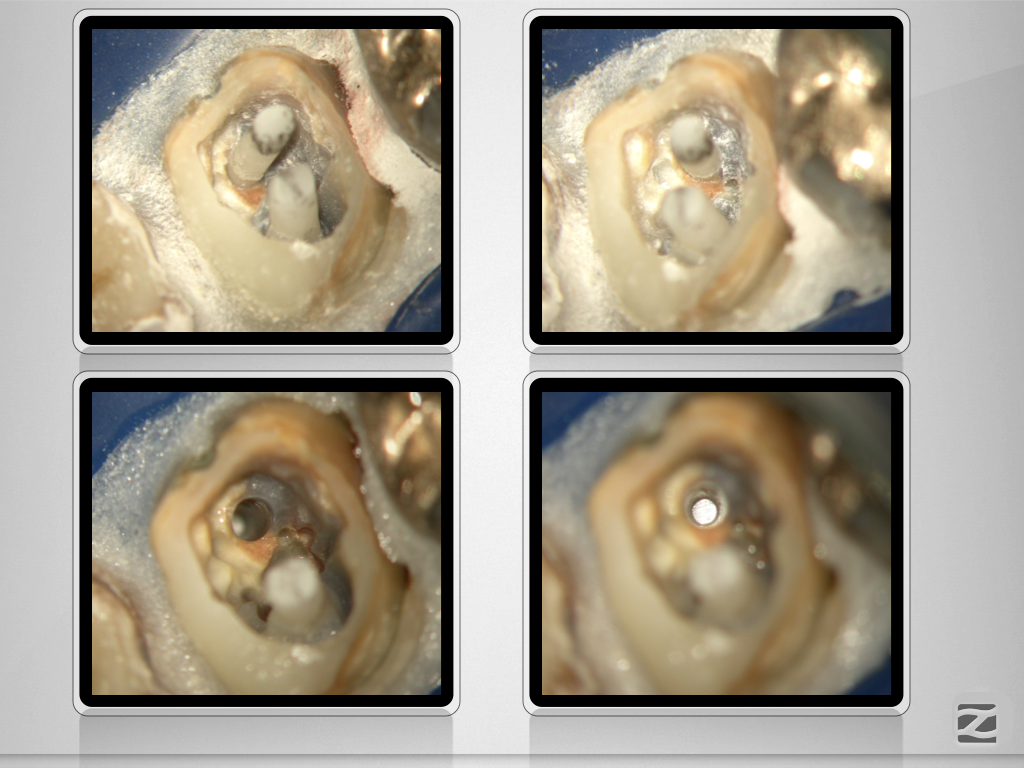

Der weiße Tod